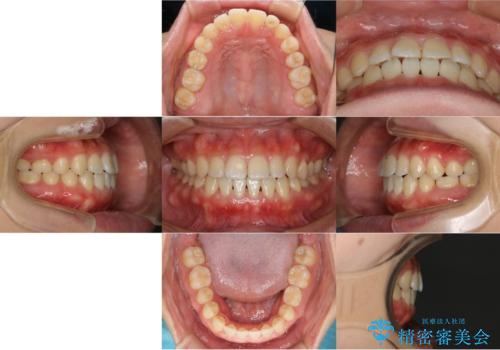

- やや受け口なのと、下の歯の隙間が気になるとのことで来院された患者様です。

下の前歯の歯茎がとても薄く、このままでは歯茎が下がってしまうリスクがありました。

また、オープンバイト(開咬)もありました。